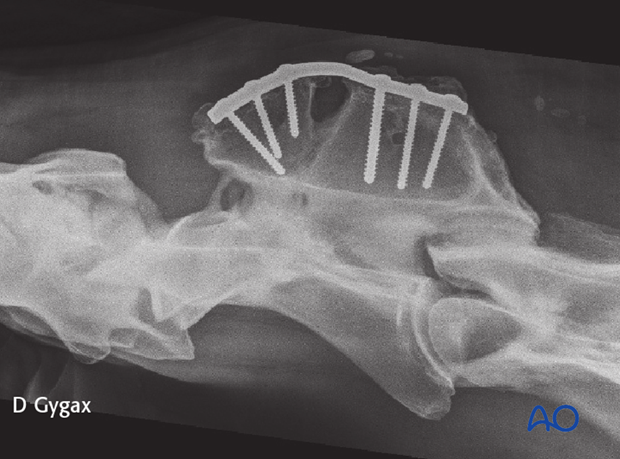

The use of the locking compression plate (LCP) is preferred for fracture fixation of the vertebrae. According to the size of the patient, a small or broad 3.5/4.0 or 4.5/5.0mm LCP is used.

Plate contouring is needed to fit the anatomical shape of the vertebra.

Accurate contouring of locking compression plates is not necessary, but it improves the closure of the soft tissue over the plate.

With the reduction forceps in position, the appropriately sized plate is applied on the dorsal spinous process.

One cortex screw is inserted into each fragment in load fashion. The correct length of the screws is determined with the help of fluoroscopy.

The remaining holes are filled with locking-head screws.

The fracture was repaired using a 7-hole 4.5mm DCP. Optimal positioning of the plate and the length of the screws were facilitated by fluoroscopy.